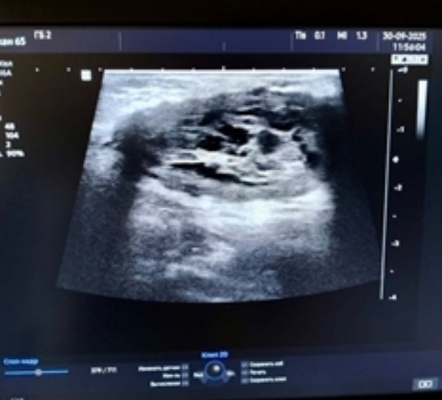

Региональный минздрав сообщает, что в конце сентября в Ульяновске городская больница №2 получила современный ультразвуковой аппарат отечественного производства — РуСкан 65. Оборудование уже активно используется специалистами.

Новый аппарат экспертного класса позволяет проводить широкий спектр исследований: сердечно-сосудистой, пищеварительной, эндокринной и половой систем, плевральных полостей, а также мягких тканей.

Благодаря функции подавления шумов устройство обеспечивает высокую чёткость изображения, что повышает точность диагностики и помогает своевременно выявлять онкопатологию. У аппарата лёгкие эргономичные монокристальные датчики, сенсорный дисплей и увеличенный экран с высоким разрешением, что снижает нагрузку на глаза. На панели управления расположены крупные кнопки с мягкой подсветкой, позволяющие не отвлекаться на настройку, а сосредоточиться на исследовании.

Фото: минздрав